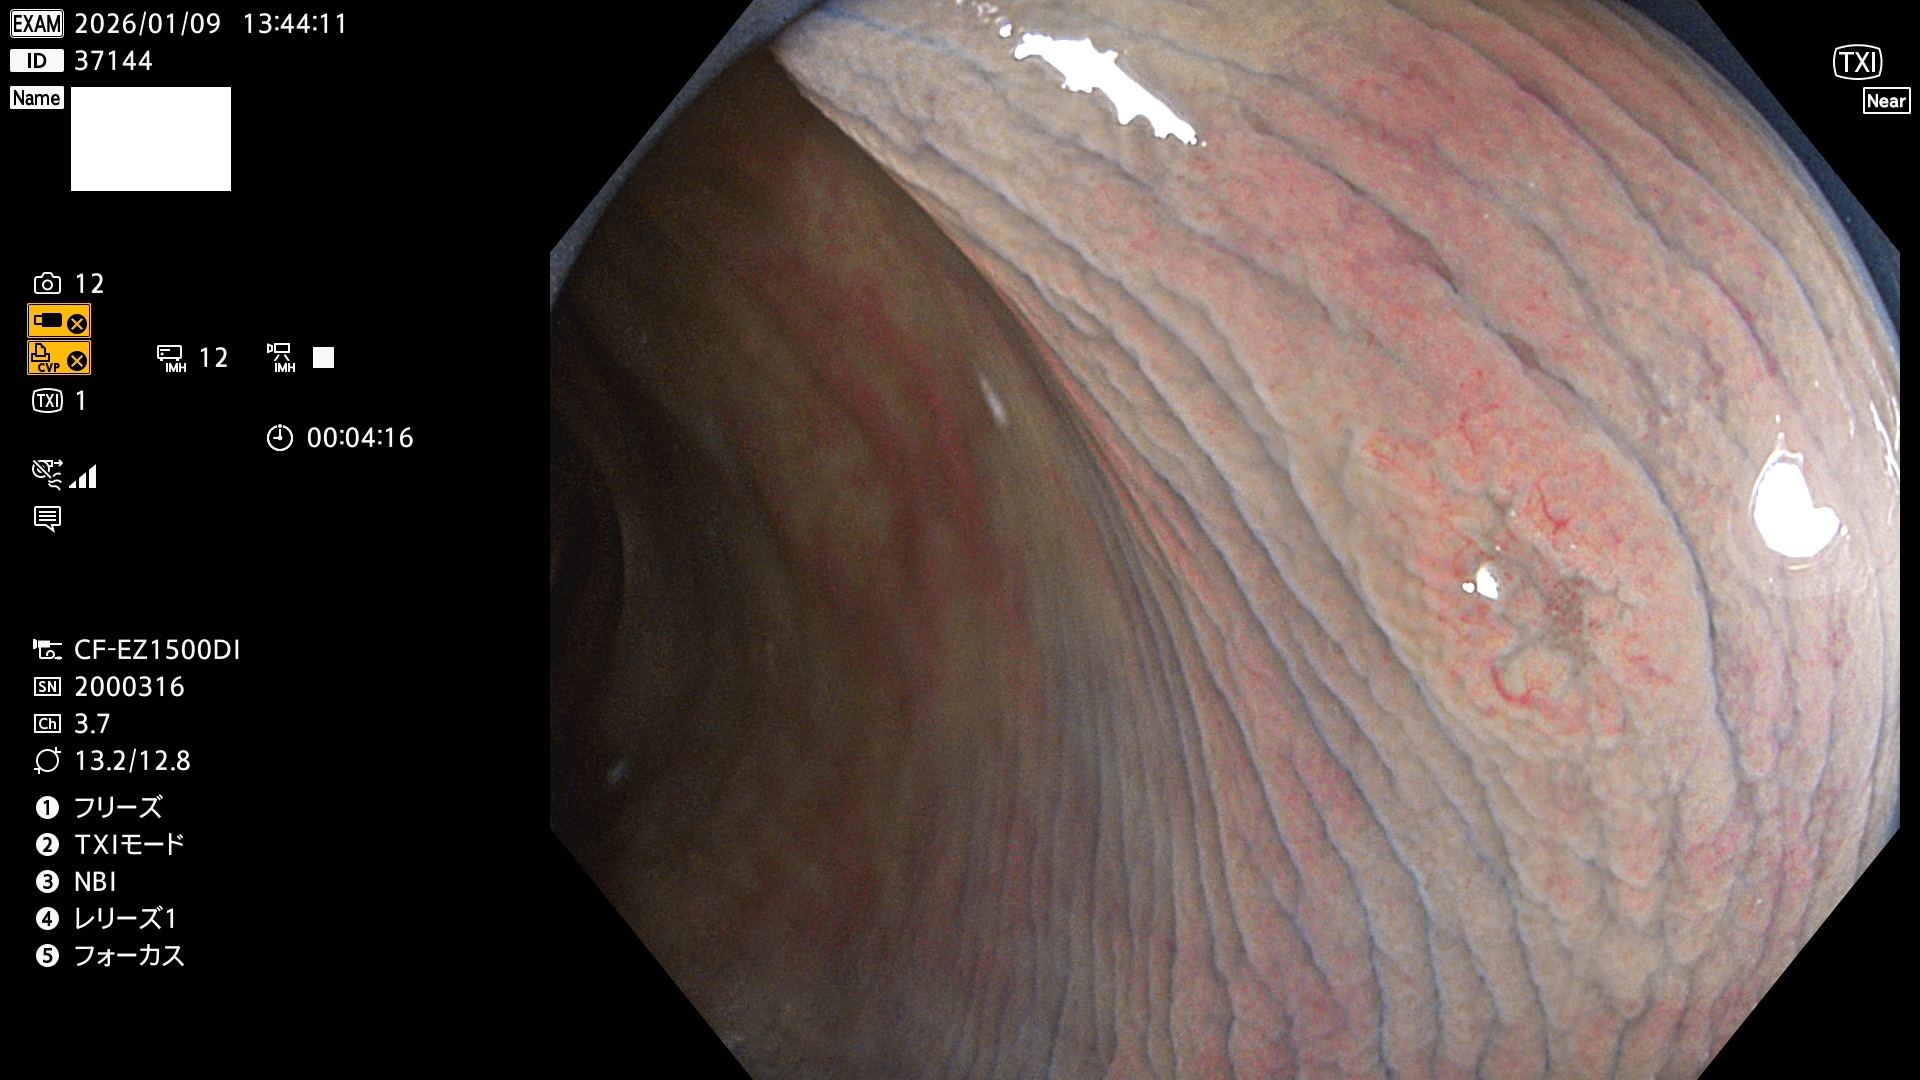

完全に平坦な物をUb、陥凹している物をUcと呼びます。Ubは認識が困難で、Ucはびらん(炎症)と紛らわしいために見落とされやすく、「内視鏡後・大腸癌」の原因になります。

専門的)Uc=De Novo癌? 内視鏡の解像度が低かった時代、このような説もありました。しかし今日の高精度内視鏡では良性の微小なUc型腺腫(APC遺伝子異常の腺腫)が日常的に見つかります。Ucこそが多段階発癌(Adenoma-Carcinoma Sequence)のMain Routeです。

毎週の検査(木・金・土・日)に発見されたUbとUc型・腺腫を、その週の日曜の夜にUPし1週間、提示します。

2026年1月8日〜1月11日の4日間(40件)6個 (Uc_ADR=6個/40人=15%)